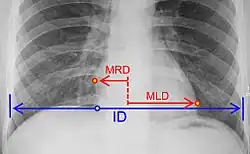

Donde: MRD = mayor diámetro perpendicular desde la línea media hasta el borde derecho del corazón MLD = mayor diámetro perpendicular desde la línea media hasta el borde izquierdo del corazón ID = diámetro interno del pecho al nivel del hemidiafragma derecho

Sobre la placa radiográfica se traza una línea que pase por el centro del tórax. Perpendicular a ésta se traza una segunda línea que llegue hasta la parte más externa del borde derecho del corazón (A) (MRD, en la imagen) y otra hasta la parte más externa del borde izquierdo (B) (MLD, en la imagen). Luego se traza otra línea que vaya del contorno interno de la caja costal derecha hasta el izquierdo, pasando tangencialmente por el borde superior del diafragma (C) (ID, en la imagen).[1]

Se realiza la división entre el diámetro transversal máximo del corazón (A + B) y el diámetro de la caja torácica en la inspiración profunda (C). Por lo general, es menor a 0,5 en los adultos; si es mayor a 0,5, se dice que hay cardiomegalia; en los niños, el índice es un poco mayor, como se muestra en la tabla que aparece a continuación.